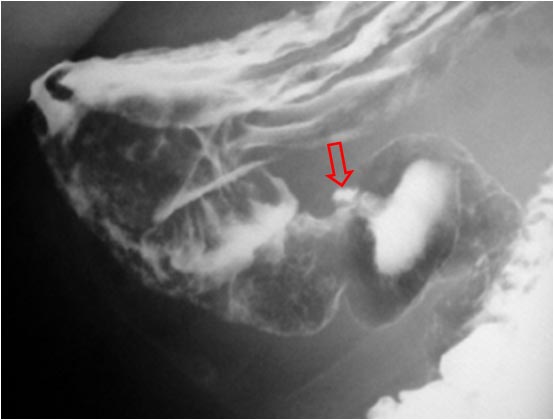

Signo visible en el tránsito baritado superior (EGD) que permite diferenciar una úlcera de una imagen de adición no ulcerosa (divertículo, pseudodivertículo, deformidad quirúrgica,…). Cuando la colección de bario es elíptica, la orientación del eje largo es un indicador del origen de la lesión. Si es paralelo a la luz indica úlcera; si es perpendicular, representa una lesión no ulcerosa.

En la imagen, una úlcera pilórica (flecha) visible como una imagen de adición de bario de forma elíptica irregular, cuyo eje mayor es paralelo a la luz antral.